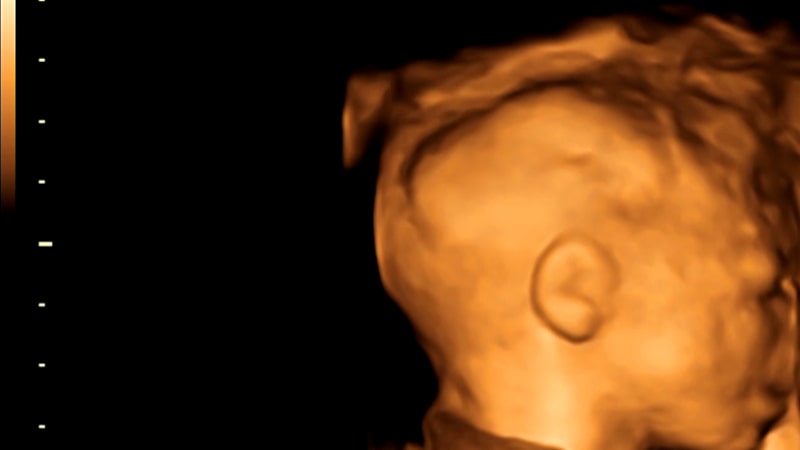

Пройти ультразвуковое обследование приглашает клиника «АБИА» – кроме отдельных процедур для будущих мам, у нас реализуются программы по комплексному ведению беременности, УЗИ-скрининги, биохимический скрининг, КТГ, 3D/4D ультразвуковое исследование.